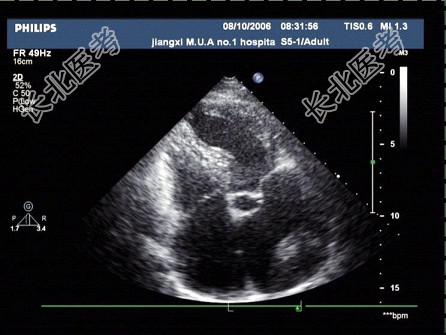

- 单项选择题一患者,超声心动图检查如图, 考虑为   (   )

A、黏液瘤

B、左房肿瘤

C、左房血栓

D、赘生物

E、以上均不是